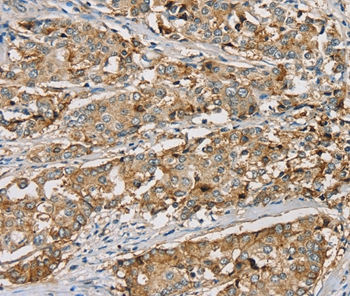

Immunohistochemical analysis of paraffin-embedded Human liver cancer tissue using #37906 at dilution 1/20.

应用详情:Immunohistochemistry: 1:25-1:100